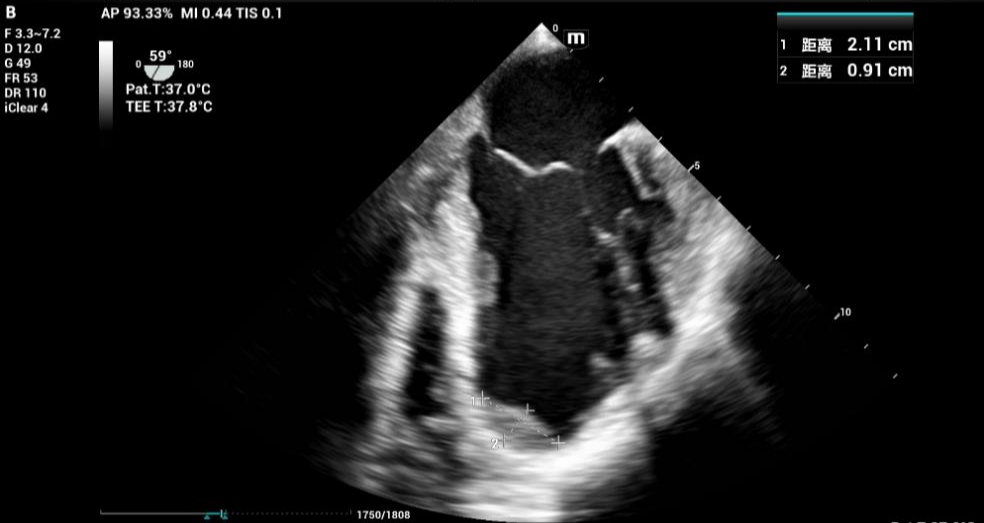

术中TEE监测下测量的血栓大小

手术当日,在麻醉科彭浩彬主治医师的操作下,TEE探头顺利置入。清晰的超声图像实时显示在大屏幕上,将心脏的每一次搏动、血栓的所有细节都尽收眼底。

手术关键操作期:TEE始终锁定左心室,确认血栓无任何移位或脱落迹象,为外科医生创造了安心操作的环境。